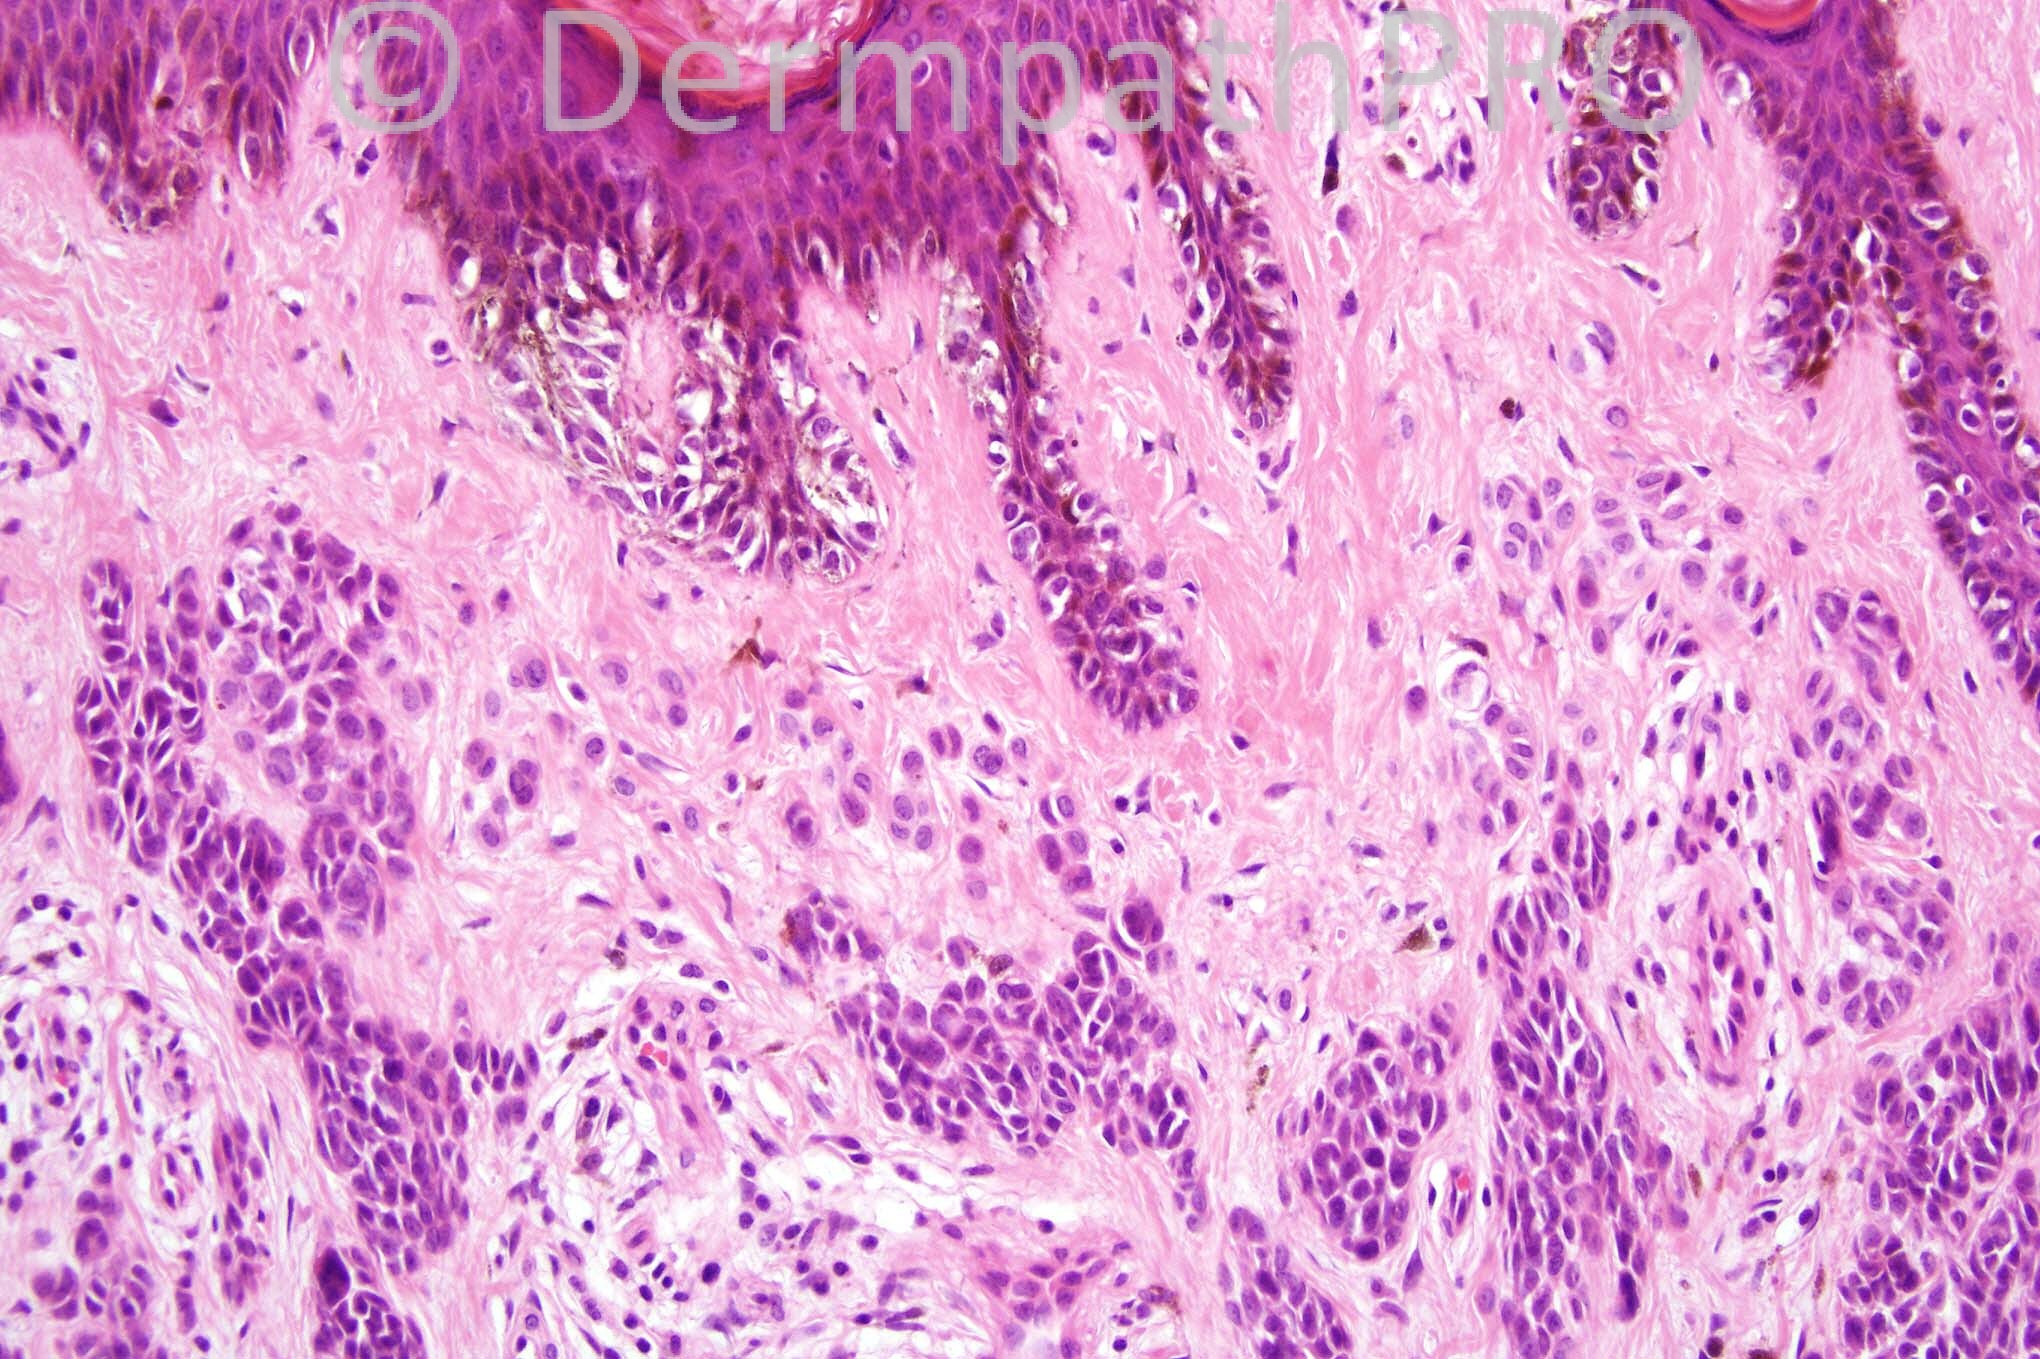

12 years-old male with a pigmented lesion on the right leg